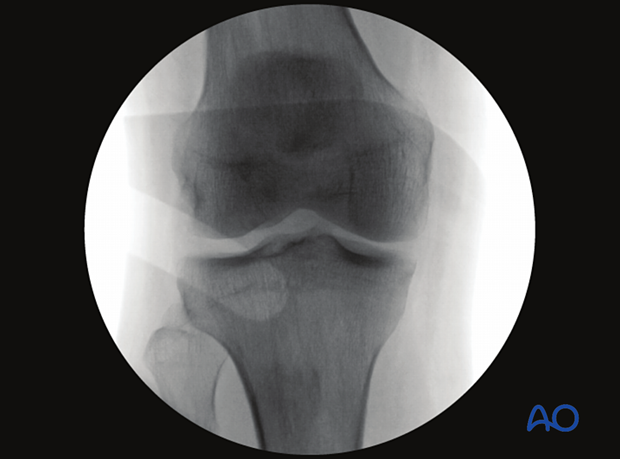

To obtain the optimal AP view of the proximal tibia:

AP images obtained with the knee in 30° flexion will not be very different from those recorded with the leg in full extension.

With the knee in 90° flexion, an AP view cannot be obtained.

The optimal AP view of the proximal tibia is obtained when:

The following lines and landmarks can be observed in the AP view of the proximal tibia:

This view is particularly useful to identify:

The correct angle between the joint line and the tibial axis (85-90°)

Images of the contralateral side may be beneficial as a reference.